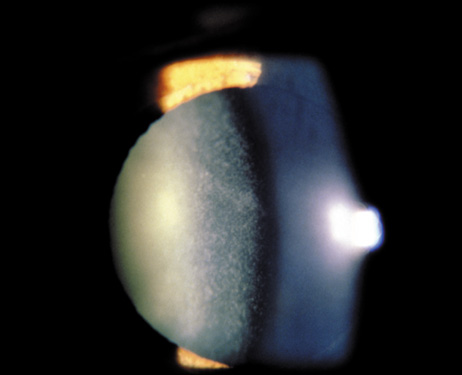

The dense bilateral lens opacities may present as a biconvex-shaped cataract or as posterior, polar, nuclear, or total cataract. The discoid lens shape may result from loss of lens material due to a posterior lens capsule defect4 or defective lens fiber formation and subsequent degeneration.5 The cataracts are present at birth, and glaucoma may be present congenitally or develop within the first 3 years of life. Other ocular findings may include corneal opacity, mitotic pupil, enophthalmos, and hypotonia.6 The cognitive impairment presents with a discrete behavioral phenotype that includes temper tantrums, irritability, complex repetitive behaviors, and unusual mannerisms. Severe renal Fanconi's syndrome may lead to progressive renal impairment. Most boys will develop a distinctive facies and habitus, and attain a height of less than 5 feet because of developmental retardation. Female carriers manifest characteristic but usually asymptomatic lenticular opacities that will correctly identify carrier status with 100% sensitivity in postpubertal females. These opacities are typically small, irregularly shaped, off-white or gray in color, nonrefractile in appearance, and distributed around the lens equator, more anteriorly than posteriorly (Figs. 1 and 2). Most importantly, and distinctively, these opacities are clustered in radial bands or wedges in the peripheral cortex of the lens and are visible by retroillumination. Typically, the opacities are moderately dense for one or two clock-hours, are then less numerous or even absent for another clock-hour or two, and so on. These opacities must be differentiated from the polychromatic, iridescent “crystals” found in Steinert's myotonic dystrophy (DM), gray-white random opacities in carriers of X-linked adrenoleukodystrophy, sutural opacities in Nance-Horan's (NH) syndrome, snowflake granules beneath the anterior and posterior capsule in diabetes mellitus, highly uniform white dots of hypoparathyroidism, and equatorial opacities in cataracta coronaria or ceruleana. Some females also manifest a dense white, central, posterior cortical cataract in the precapsular area. Although the posterior central cataract is apparently congenital, the equatorial and anterior cortical punctate opacities are uncommon in prepubertal female Lowe's syndrome carriers.7 Carrier status may also be confirmed by DNA diagnosis.

Fig. 2. OCRL. Retroillumination of small, irregularly shaped, nonrefractile anterior cortical opacities in the lens of a female carrier of OCRL. (Courtesy of Dr. R.A. Lewis, Baylor College, Houston, Texas.)